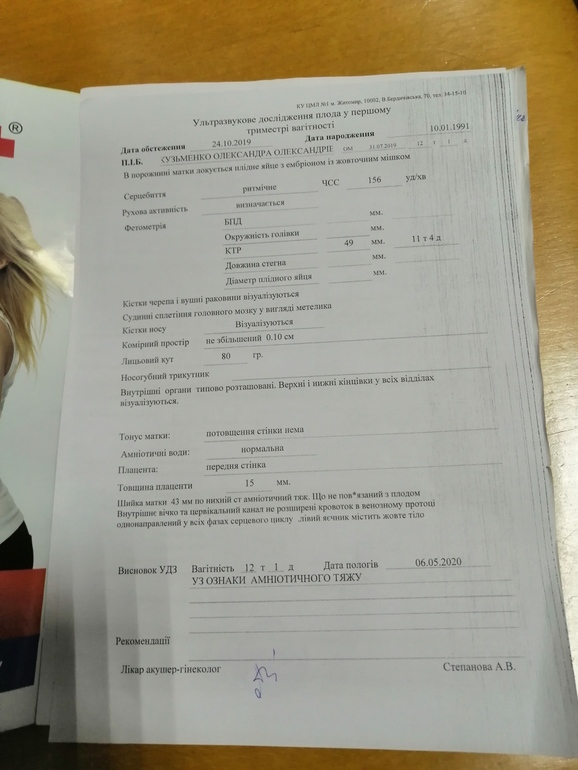

Хорошо, что заранее записалась на узи в частную клинику, там узистка хорошая и аппарат. В итоге тяжа нету, всё измеряли, всё хорошо)))

Узи с частной